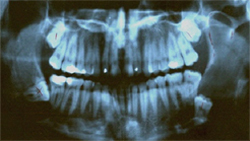

There are a variety of impacted wisdom teeth positions including mesial, distal, horizontal, vertical, soft tissue, and bony. These terms refer to the angle (positioning) of impacted wisdom teeth. The most common form is mesial impacted wisdom teeth, which means the tooth is angled forward (towards the front of the mouth.)

The simplest explanation of this dental problem is that the wisdom tooth has not emerged into its expected position either by improper angulation, lack of room in the jaw for more teeth, or obstruction by existing teeth.